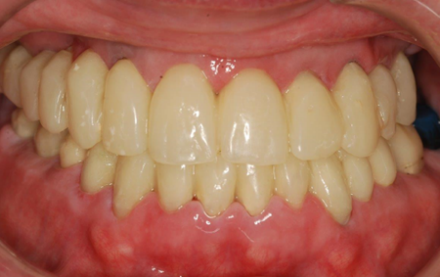

When all of a patient’s teeth are failing but dentures aren’t an option, we perform “staged therapy.” First, every tooth is prepared and fitted with a full-arch temporary splint (Fig. 1). Next, select teeth are extracted and replaced with implants, while the remaining teeth continue to hold the temporary (Fig. 2 & 3). In Stage II, abutments are seated on existing implants, the remaining teeth are extracted, and implants placed (Fig. 4). Finally, a permanent fixed splint is secured on all implants (Figs. 5 & 6).

Fig. 2: Stage Ia Temporary Splint Providing Aesthetics and Function

Fig. 3: Stage Ib Three Teeth Extracted and Replaced with Implants

Stage I: Clean up the decay on all of her remaining upper teeth, prepare them (Fig. 1) and insert an aesthetic temporary splint (Fig. 2). This was followed by the strategic extraction of several teeth, replacing them with implants, while the remaining teeth held the temporary bridge (Fig. 3).